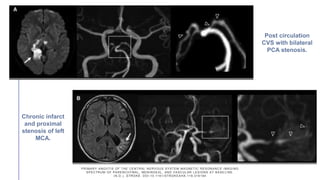

Post circulation

PCA stenosis.

and proximal

MCA.

PRIMARY ANGIITIS OFTHE CENTRAL NERVOUS SYSTEM MAGNETIC RESONANC E IMAGING SPECTRUM OF PARENCHYMAL, MENINGEAL, AND VASCULAR LESIONS AT BASE LINE. (N.D.). STROKE. DOI:10.1161/STROKEAHA.116.016194 Post circulation CVS with bilateral PCA stenosis. Chronic infarct and proximal stenosis of left MCA.